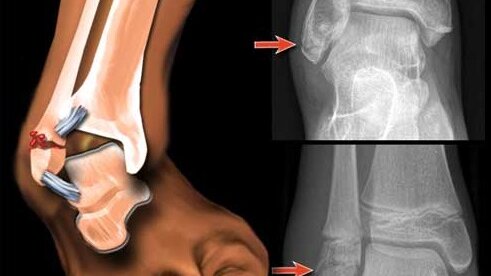

Перелом Латеральной лодыжки.

Как-то раз, я вышел из трамвая! вижу горит зелёный! свет светофора, и он начинает мигать, я решила побежать. Бегу и спотыкаюсь об поребрик . В этот момент я был в наушниках и слушал песню Джарахова я в моменте! И в этом моменте я лечу на дорогу на проезжую часть! Я не понимаю что происходит! я как в тумане! мимо меня проходят люди!! я пытаюсь встать но не могу. Ко мне подходит мой друг! (мы с ним ехали в трамвае) он меня подымает, но я не могу встать ! ко мне подходит какой-то мужчина , и помогает тоже встать мы на проезжей части стоим ...